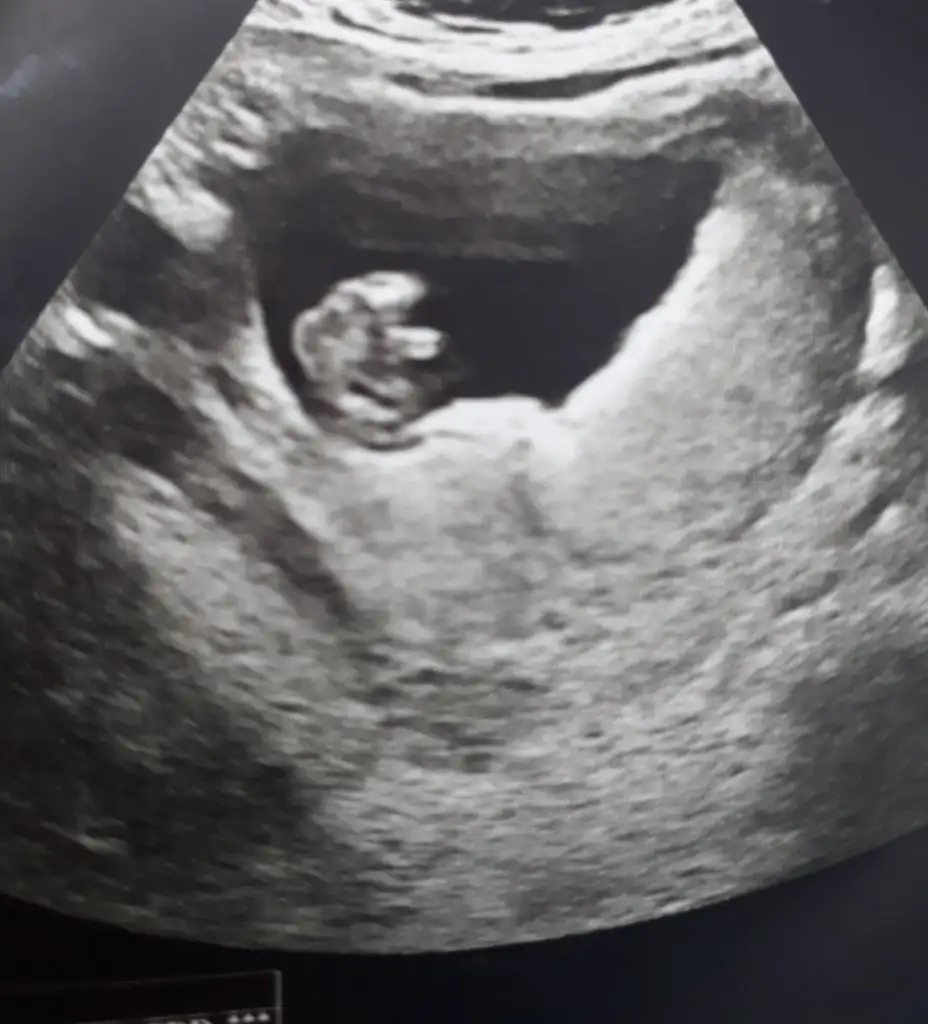

T tulperde cnm CRL 60.7

Nuchal 1.2

Nazal kemik gözlendi

Duktus venozus akımı normal majör fetal anatomik bozukluk saptanmadı.

FHR 162bpm yazıyor yorumlar misin

Ultrason ölçümlerin gayet normal çıkmış canım. 😍

Kan değerlerin de normal çıkarsa risksiz gelir test sonucun inşallah 🤲